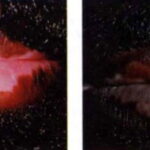

In vitiligo, melanocytes in the bulb and infundibulum of the hair follicle are

often destroyed; but the lower and middle portions of the follicle as well as the outer root sheath are spared. PUVA stimulates follicular melanocytes to migrate into the epidermis and repopulate the surrounding depigmented skin, possibly as a result of the release of cytokines and chemotactants from the epidermal keratinocytes .

Topical PUVA is sometimes used in patients whose vitiligo involves less than 20 percent of the body surface area . However, unwanted side effects are common and include cosmetically displeasing hyperpigmentation of skin surrounding vitiligo areas due to inadvertent psoralen application, severe phototoxicity reactions, and intense pruritus. Oral psoralens are used for patients with more extensive involvement or in patients who do not respond to topical PUVA .